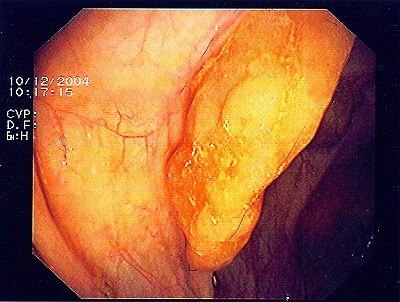

Nach einem speziellen kombinierten Manöver (laparaskopisch gestützte Koloskopie - gleichzeitige Bauch- und Darmspiegelung), gelingt es, den Polyp weit im Gesunden mit einem speziellen Klammernahtgerät zu entfernen, wobei die hier abgebildete Klammernahtreihe zurück bleibt. Der Eingriff erfolgt - wie gesagt - in so genannter Schlüssellochtechnik, aber auch mit unterstützender Darmspiegelung.

Wie bei den Abbildungen 29 und 31 erfolgt hier nach einem speziellen kombinierten Manöver (laparasko typisch gestützte Koloskopie - gleichzeitige Bauch- und Darmspiegelung), Entfernung des Polypen weit im Gesunden mit einem speziellen Klammernahtgerät. Die hier gut abgebildete Klammernahtreihe bleibt zurück. Der Eingriff erfolgt - wie gesagt - in so genannter Schlüssellochtechnik, aber auch mit unterstützender Darmspiegelung.